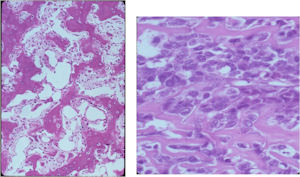

Gross Pathology

The gross pathology of an osteoblastoma is indistinguishable from an osteoid osteoma except larger

- Nidus is well demarcated

- Granular, friable, reddish hemorrhagic tissue

- May bleed significantly when curetted

- Cortex is thinned, possibly destroyed

Microscopic Pathology

- Interlacing network of bone trabeculae in a loose fibrovascular stroma

- Prominent vessels

- Osteoblasts are plump, active, scattered mitotic figures

- Osteoblasts line up around periphery of trabeculae (Osteoblastic Rimming)

- Soft tissue component usually surrounded by shell of reactive bone or periosteum (Egg Shell Rim of Calcification)